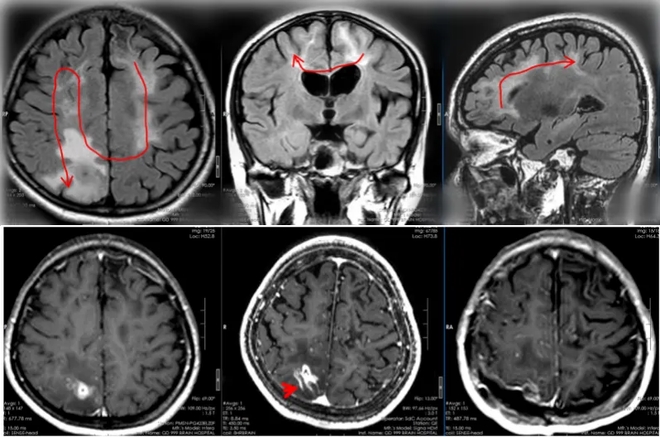

Trong hai năm qua, bệnh nhân này vẫn kiên trì dùng thuốc và khám sức khỏe định kỳ, không còn bị động kinh nữa. Tuy nhiên, chân phải của cô tiếp tục yếu và trí nhớ cũng suy giảm. Vào ngày 20/4 vừa qua, các bác sĩ cuối cùng đã phát hiện con giun ký sinh di chuyển đến vùng không còn chức năng của thùy đỉnh bên phải của bệnh nhân.

Chớp lấy thời cơ, 3 ngày sau, bệnh nhân được thực hiện ca phẫu thuật mở hộp sọ cho bệnh nhân, không chỉ "bắt" thành công một con giun dài 20cm còn sống , mà còn loại bỏ được "tổ giun" (u hạt viêm).